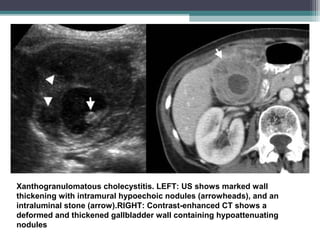

Xanthogranulomatous cholecystitis

• Xanthogranulomatous cholecystitis is an unusual variant of chronic cholecystitis,

characterized by a lipid-laden benign , destructive , inflammatory process

comparable to xanthogranulomatous pyelonephritis.

• Etiology : Rupture of occluded RAS ( Rokitansky –Aschoff Sinuses ) with extrusion

of bile into the gall bladder wall that elicits an inflammatory reaction .

• The inflammatory reaction can obliterate soft tissue planes and extend into

nearby structures, mimicking tumour invasion.

• IMAGING :

• USG : Cholelithiasis and gall bladder wall thickening ( focal or diffuse )

Most characteristic finding : Presence of hypoechogenic nodules or bands in the

Gall bladder wall .

• CT : Show marked gallbladder wall thickening, often containing intramural

nodules that are hypoechoic at sonography and hypoattenuating representing

abscesses or foci of xanthogranulomatous inflammation.

• MRI: focal or diffuse areas of T2 and low T1 signal which shows delayed

enhancement with gadolinium.

• It is important for the radiologist to distinguish xanthogranulomatous cholecystitis

from gallbladder cancer.

• FEATURES TO DIFFERENCIATE XGN CCS Vs GB CARCINOMA :

• The characteristic CT and MRI fi ndings of xanthogranulomatous cholecystitis—

including a patent mucosal line or luminal surface enhancement on CT, and

intramural nodules with hypoattenuation on CT or very high signal intensity on

T2-weighted images—can be helpful in differentiating the two conditions

Xanthogranulomatous cholecystitis. LEFT: US shows marked wall

thickening with intramural hypoechoic nodules (arrowheads), and an

intraluminal stone (arrow).RIGHT: Contrast-enhanced CT shows a

deformed and thickened gallbladder wall containing hypoattenuating

nodules

Xanthogranulomatous cholecystitis. LEFT:US shows marked wall thickening with intramural hypoechoic nodules (arrowheads), and an intraluminal stone (arrow).RIGHT: Contrast-enhanced CT shows a deformed and thickened gallbladder wall containing hypoattenuating nodules